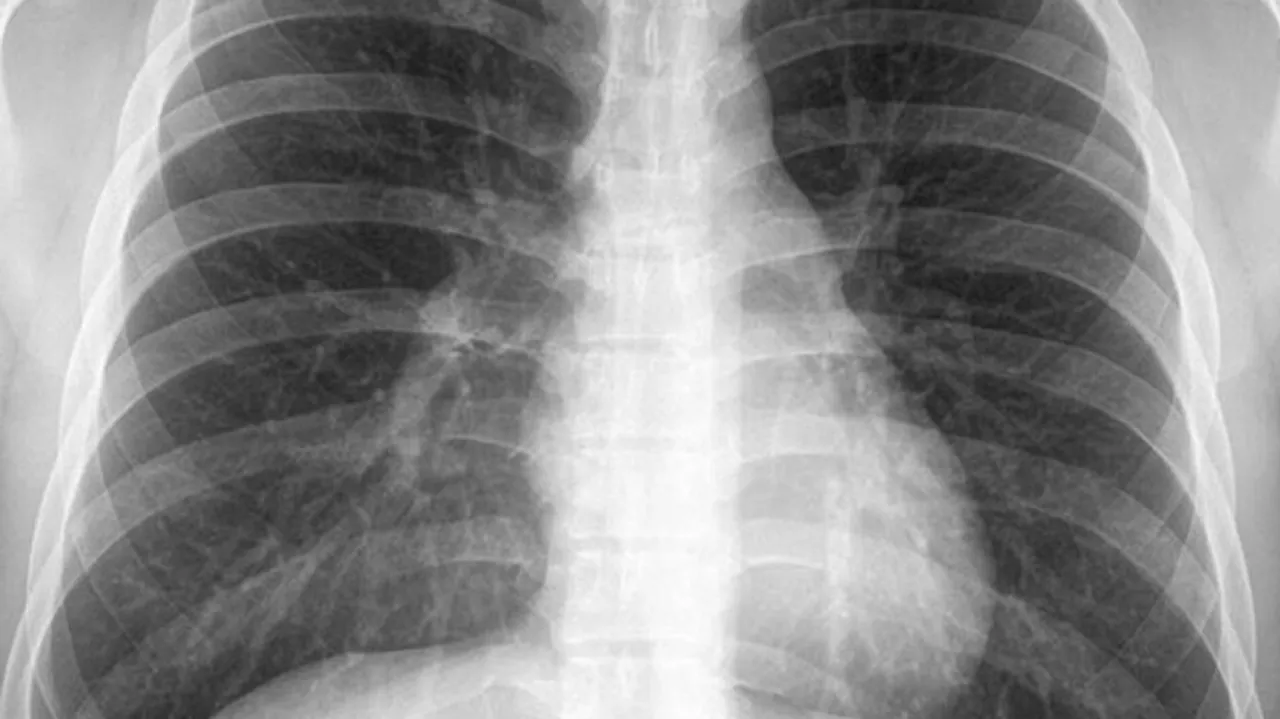

Chest X-Ray

Researchers at the Indian Institutes of Technology Jodhpur (IIT-J) have developed an Artificial Intelligence (AI) based chest X-Ray technique for Covid-19A screening.

The team proposed a deep learning-based algorithm called COMiT-Net, which learns the abnormalities present in the chest X-Ray images to differentiate between a Covid affected lung and a non-Covid affected lung.

The AI algorithm not only predicts whether a person has Covid-19 pneumonia, but it is also capable of identifying the infected regions in the lungs, thus making them explainable.

The new technique can visually showcase the region which is infected. It interprets only from the lung region.